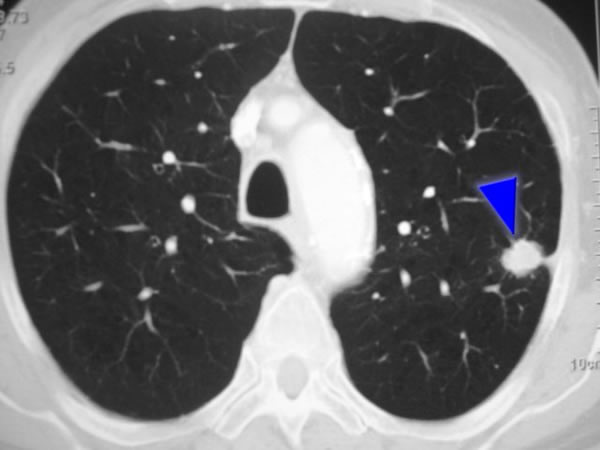

Supervivencia global con nivolumab neoadyuvante más quimioterapia en el cáncer de pulmón

21 agosto 2025

Tres ciclos de nivolumab neoadyuvante más quimioterapia mejoraron significativamente la supervivencia general en pacientes con cáncer de pulmón no microcítico resecable, en comparación con la quimioterapia sola. New England Journal of Medicine, agosto de 2025.